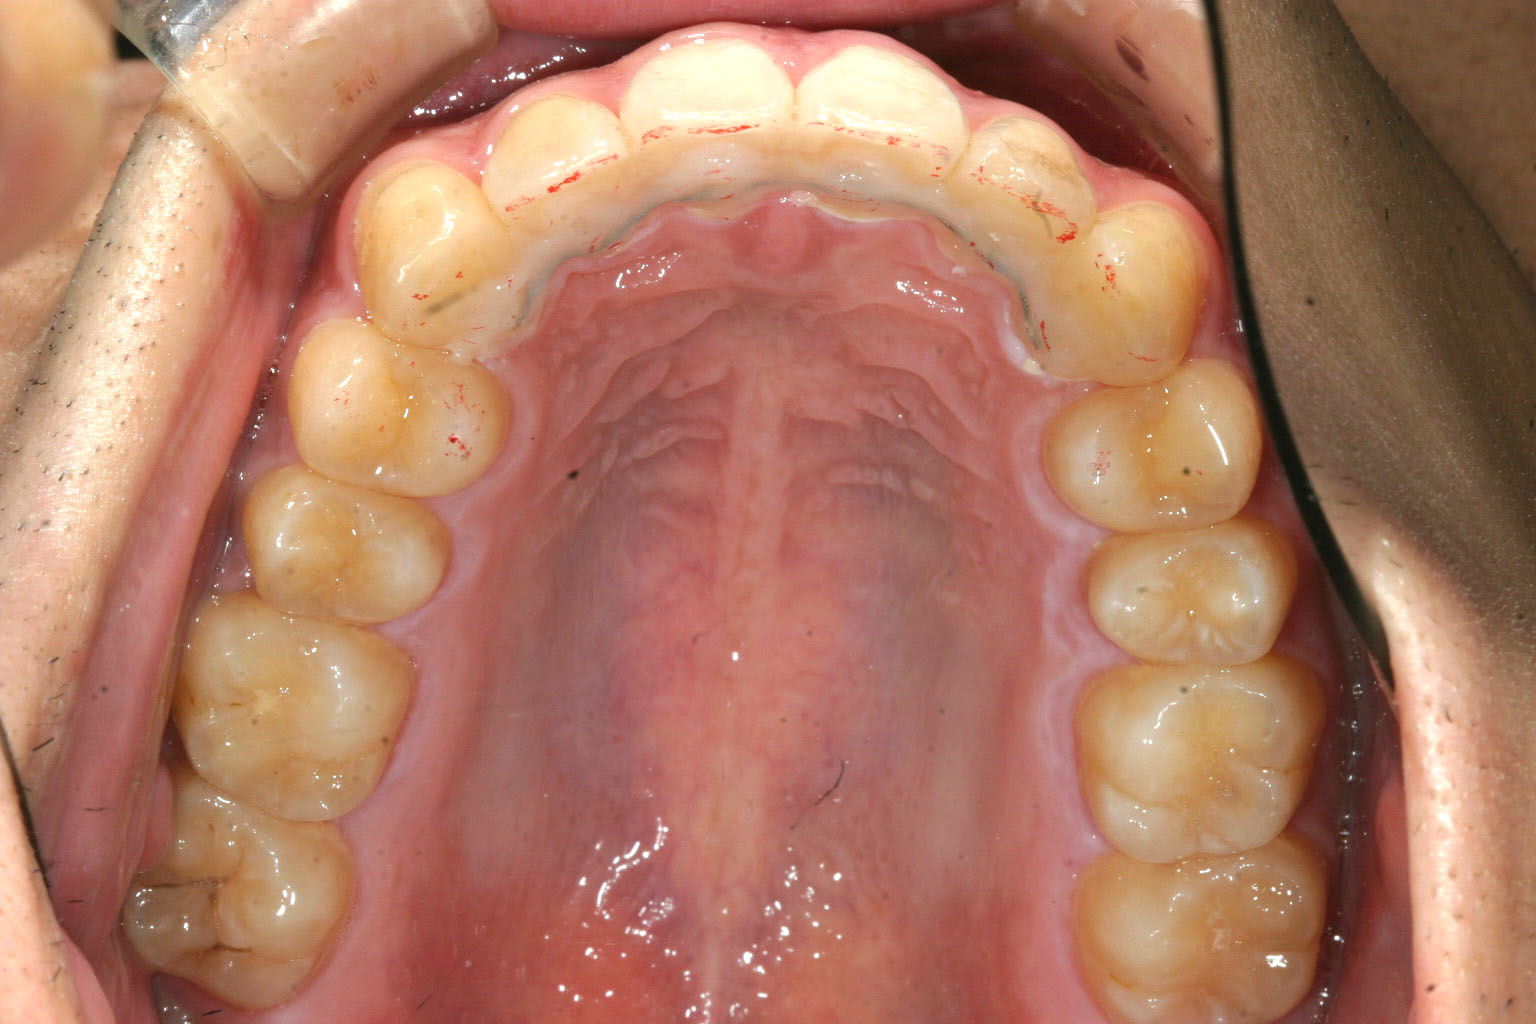

非抜歯で歯列のを広げました。

かなり入りました。

今回のケースは患者様の希望で抜歯せずに最大限に出っ歯を改善しました。

狭くなったアーチフォームの改善とインビザラインの得意技であるIPR(歯と歯の隙間を削る)を行う事によりここまで非抜歯でも改善できると言う症例です。